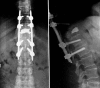

Percutaneous minimally invasive versus open spine surgery in the treatment of fractures of the thoracolumbar junction: a comparative effectiveness review

Objective: To determine the comparative effectiveness and safety of percutaneous minimally invasive versus open spine surgery for fractures of the thoracolumbar junction.

Results: • Two studies (Level of Evidence III) met our inclusion criteria. • Radiographic outcomes were similar between treatment groups. • Postoperative incisional pain was less in patients undergoing percutaneous MIS. • Patient function as assessed by the Hannover Spine Score, the SF-36 and the MacNab criteria were slightly higher in the percutaneous minimally invasive group, but not statistically significant. • Percutaneous MIS resulted in less blood loss and shorter length of hospital stay than open surgery. • No complications were reported using percutaneous MIS.

Conclusion: Limited data suggest that percutaneous techniques are associated with less postoperative pain, less blood loss, a shorter hospital stay, and a slightly better functional outcome. However, concerns remain on the effectiveness of percutaneous techniques in correcting spinal deformity and achieving bony fusion. Further studies are needed to verify these preliminary findings.